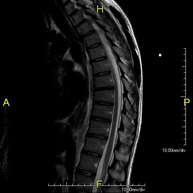

Prueba diagnóstica no invasiva que consiste en la obtención de imágenes de alta definición anatómica de la columna cervical mediante el empleo de un campo electromagnético y ondas de radio (con un emisor y un receptor). No utiliza radiación ionizante. Indicaciones: traumatismo, degeneración de la columna, hernias. - RM Columna dorsal

Prueba diagnóstica no invasiva que consiste en la obtención de imágenes de alta definición anatómica de la columna dorsal, mediante el empleo de un campo electromagnético y ondas de radio (con un emisor y un receptor). No utiliza radiación ionizante. Indicaciones: traumatismo, problemas degenerativos, hernias, tumores. - RM Columna lumbar

Prueba diagnóstica no invasiva que consiste en la obtención de imágenes de alta definición anatómica de la columna dorsal mediante el empleo de un campo electromagnético y ondas de radio (con un emisor y un receptor). No utiliza radiación ionizante. Indicaciones: traumatismo, problemas degenerativos, hernias, tumores. - RM Columna Lumbar